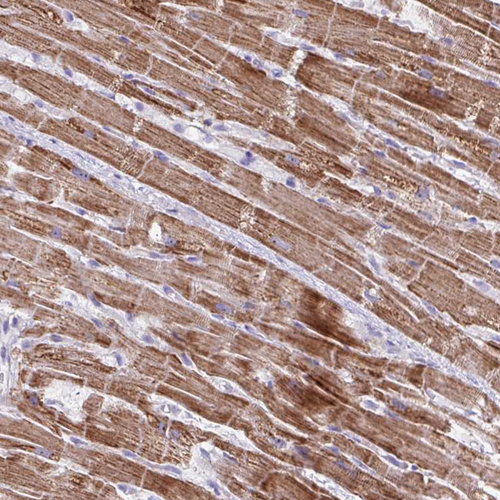

Immunohistochemical staining of human Heart muscle shows strong granular cytoplasmic positivity in cardiomyocytes.